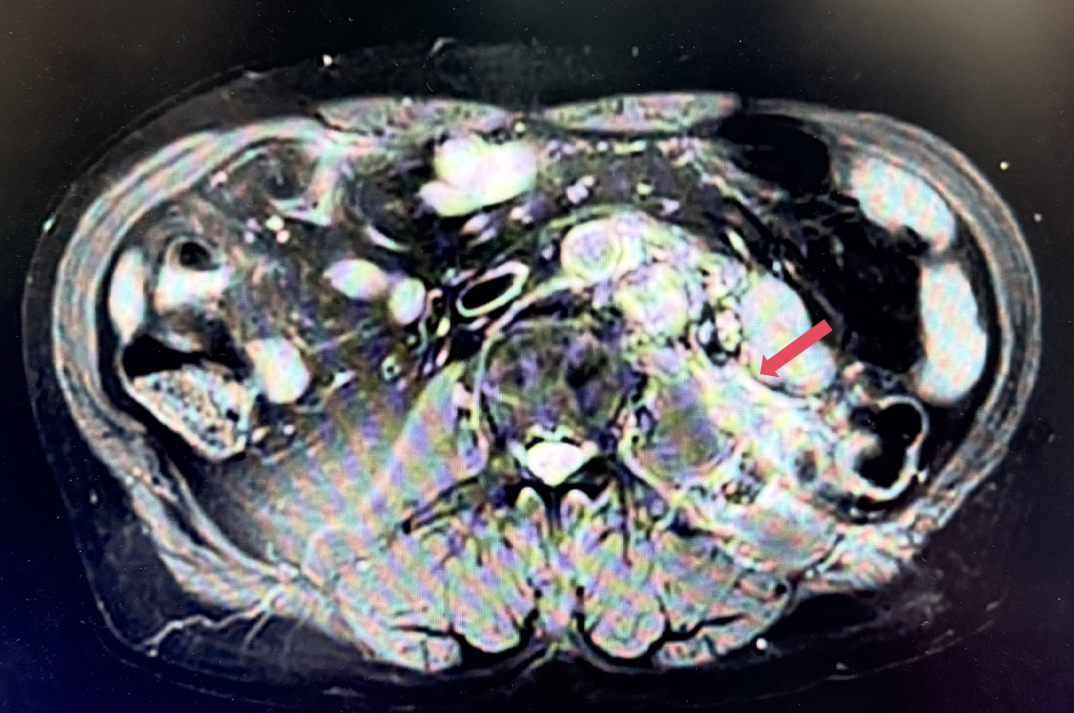

2023年1月,基线

2023年3月:用药6周(C2)后首次肿评,肿瘤负荷减少至76.8mm,达到PR。